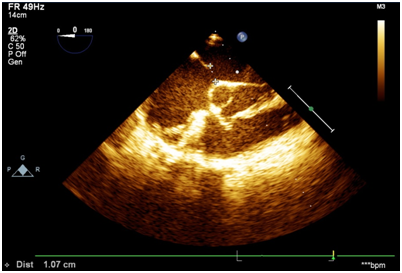

2D-echo of his sibling also showed RA and RV enlargement. TEE showed ostium secundum atrial septal defect with left to right shunt. (Figure 4)